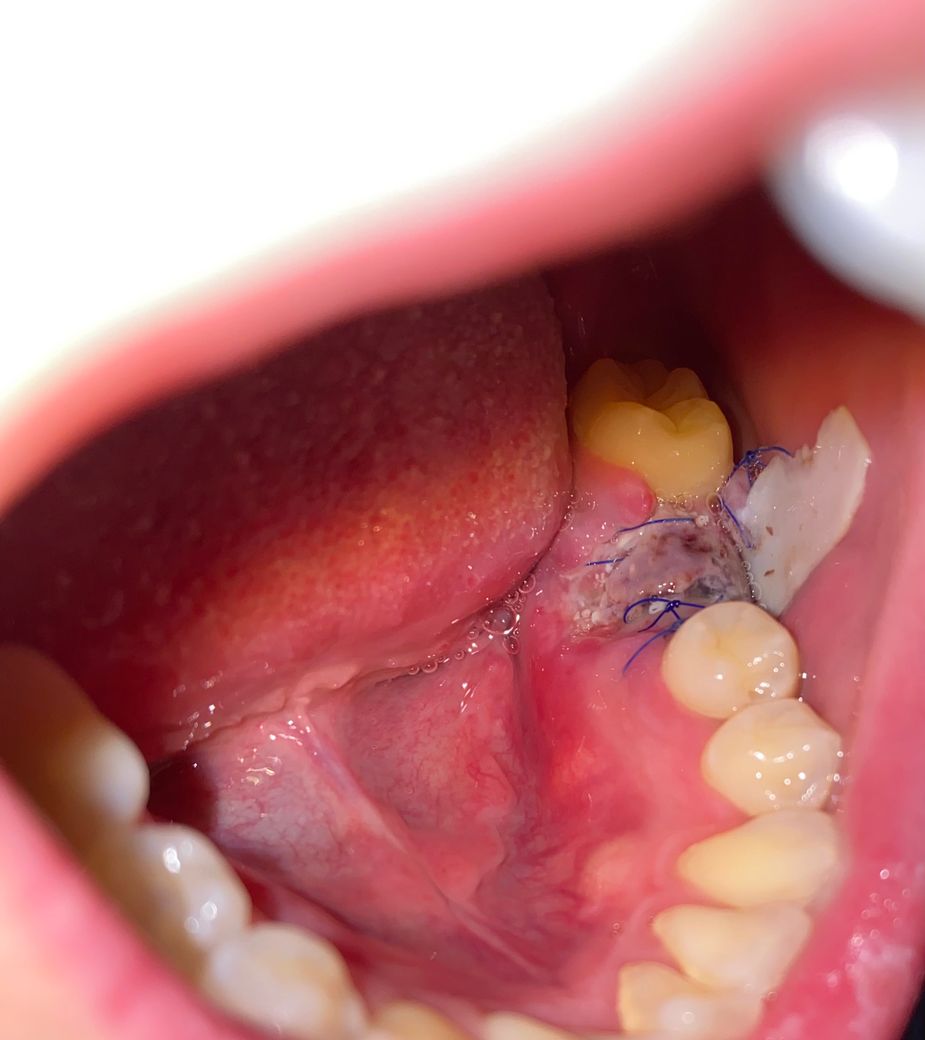

뼈이식 이후 멤브레인이 떨어졌는데 괜찮나요?

임플란트를 위한 발치 및 뼈이식 이후 9일째입니다. 이전에 실밥이 하나둘 풀리더니 멤브레인이라 부르는 막이 물을 마실때나 음식을 먹을때 사진과 같이 뒤집어집니다. 한쪽은 아예 떨어졌고 반대편도 간당간당합니다. 내부 사진을 첨부합니다. 혹시 이 막이 떨어진것과 현재 내부 상태가 괜찮은건지 소견을 듣고싶습니다.

멤브라인 막이 구강 내 노출되는 경우는 있으나 저렇게 달랑달랑하게 되진 않습니다. 현재 사진상 보면 잇몸 치유를 위해 붙여둔 구강 내 반창고 같은 것일 확률이 높고 그건 떨어져도 어쩔 수 없습니다.

인조막 멤브레인은 떨어졌지만 멤브레인 아래쪽은 정상적으로 육아조직으로 덮혀 정상적으로 아물고 있는 것으로 보입니다. 빨리 치과에 도로 가서 멤브레인은 제거하는 것이 좋습니다.

멤브레인이 떨어지면 뼈이식한게 흩어질수도 잇으니 치과에 가셔서 후처치를 다시 받으시는게 좋을것같습니다 .